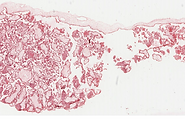

Ovario- H-E-40X